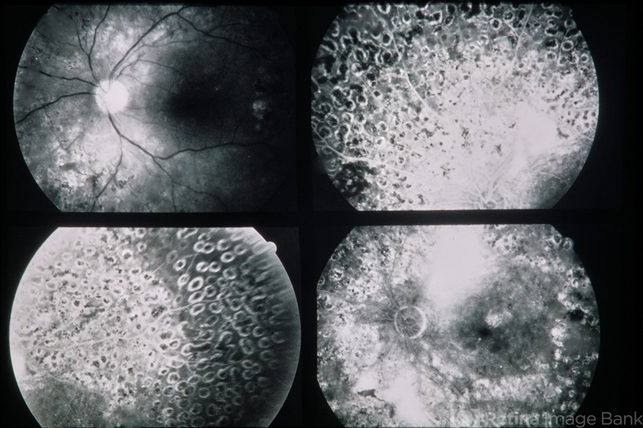

- PDR

- 35-year-old white male. RE 3/200 LE 20/32. Proliferative diabetic retinopathy.